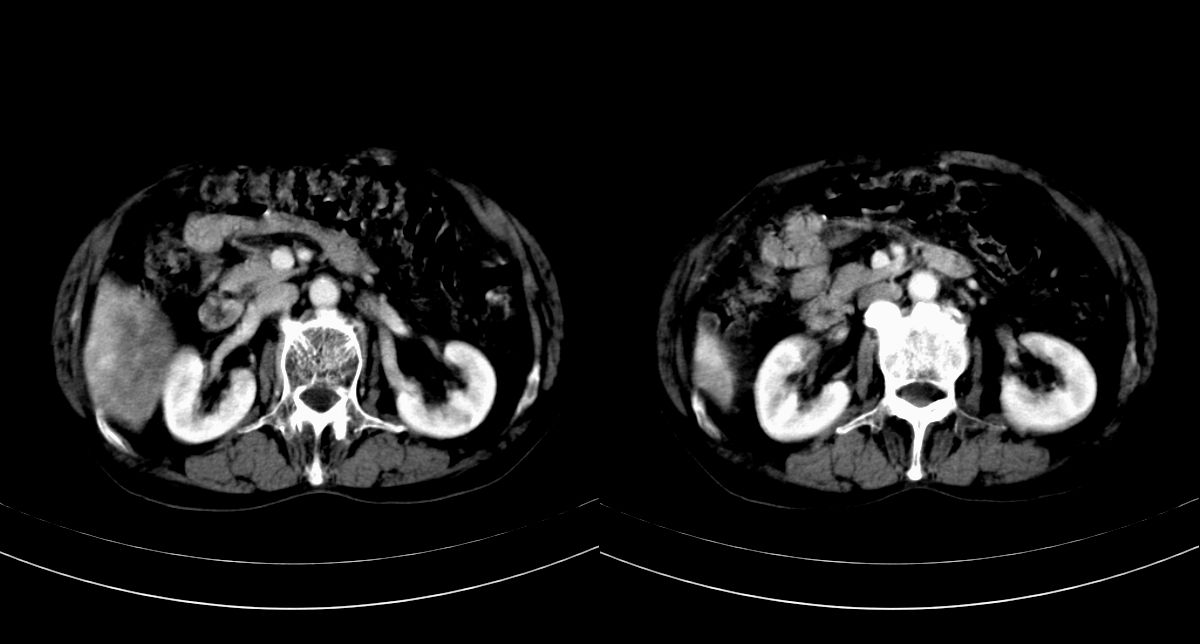

男,79y,无不适。体检发现肝脏占位。

肝内多发低密度结节,增强动脉期明显强化,门脉期逐渐下降,内有液化坏死区。

肝内多发低密度结节灶,增强动脉期明显不规则环状强化,;门脉期逐渐下降,肿瘤壁厚薄不一,内有坏死液化区。